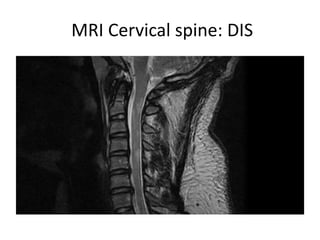

MRI Cervical spine: DIS

Dissemination in Space

Polman CH et al, Ann Neurol 2011; 69:292–302

DIS demonstrated by 2 :

1- MRI brain

2. MRI cord

3. CSF oligoclonal bands